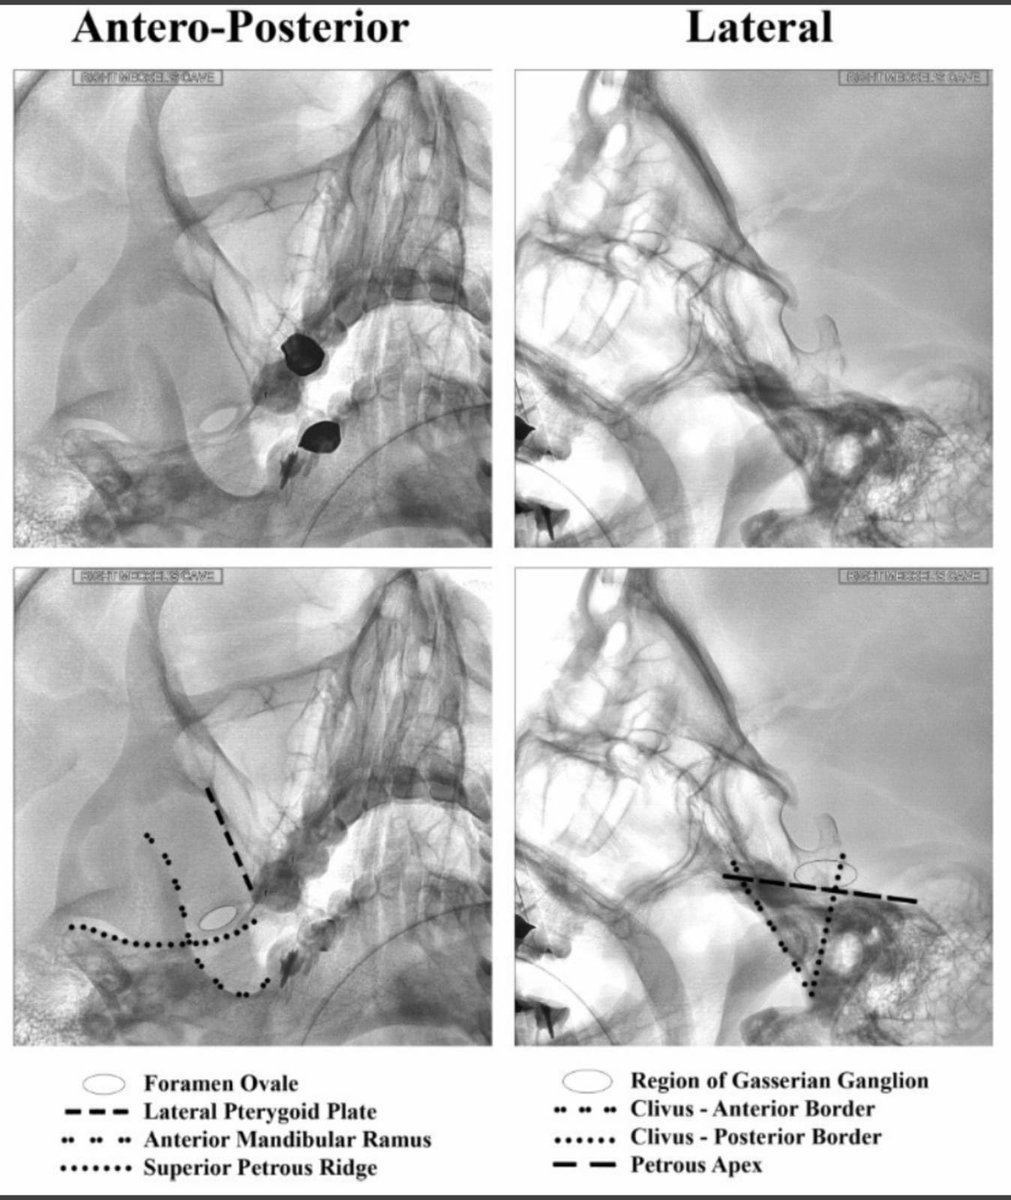

Severe facial pain after Failed MVD (micro vascular decompression) surgery for #Trigeminalneuralgia. Did RFA for this patient today. Difficult case as CSF was everywhere due to distorted anatomy. Selective mandibular/maxillary division ablated near the foramen. #Trigeminal

tariqtramboo's tweet image. Severe facial pain after Failed MVD (micro vascular decompression) surgery for #Trigeminalneuralgia. Did RFA for this patient today. Difficult case as CSF was everywhere due to distorted anatomy. Selective mandibular/maxillary division ablated near the foramen.  #Trigeminal

Radiofrequency procedure for #Trigeminal Neuralgia done just now at #Reliefpainservice kashmir. No sedation given. Pulsed RFA for 300 sec, before conventional RFA desensitises the ganglion for heated ablation (RFA). Patient did not require any sedation during the procedure.

tariqtramboo's tweet image. Radiofrequency procedure for #Trigeminal Neuralgia done just now at #Reliefpainservice kashmir.

No sedation given. Pulsed RFA for 300 sec, before conventional RFA desensitises the ganglion for heated ablation (RFA). Patient did not require any sedation during the procedure.